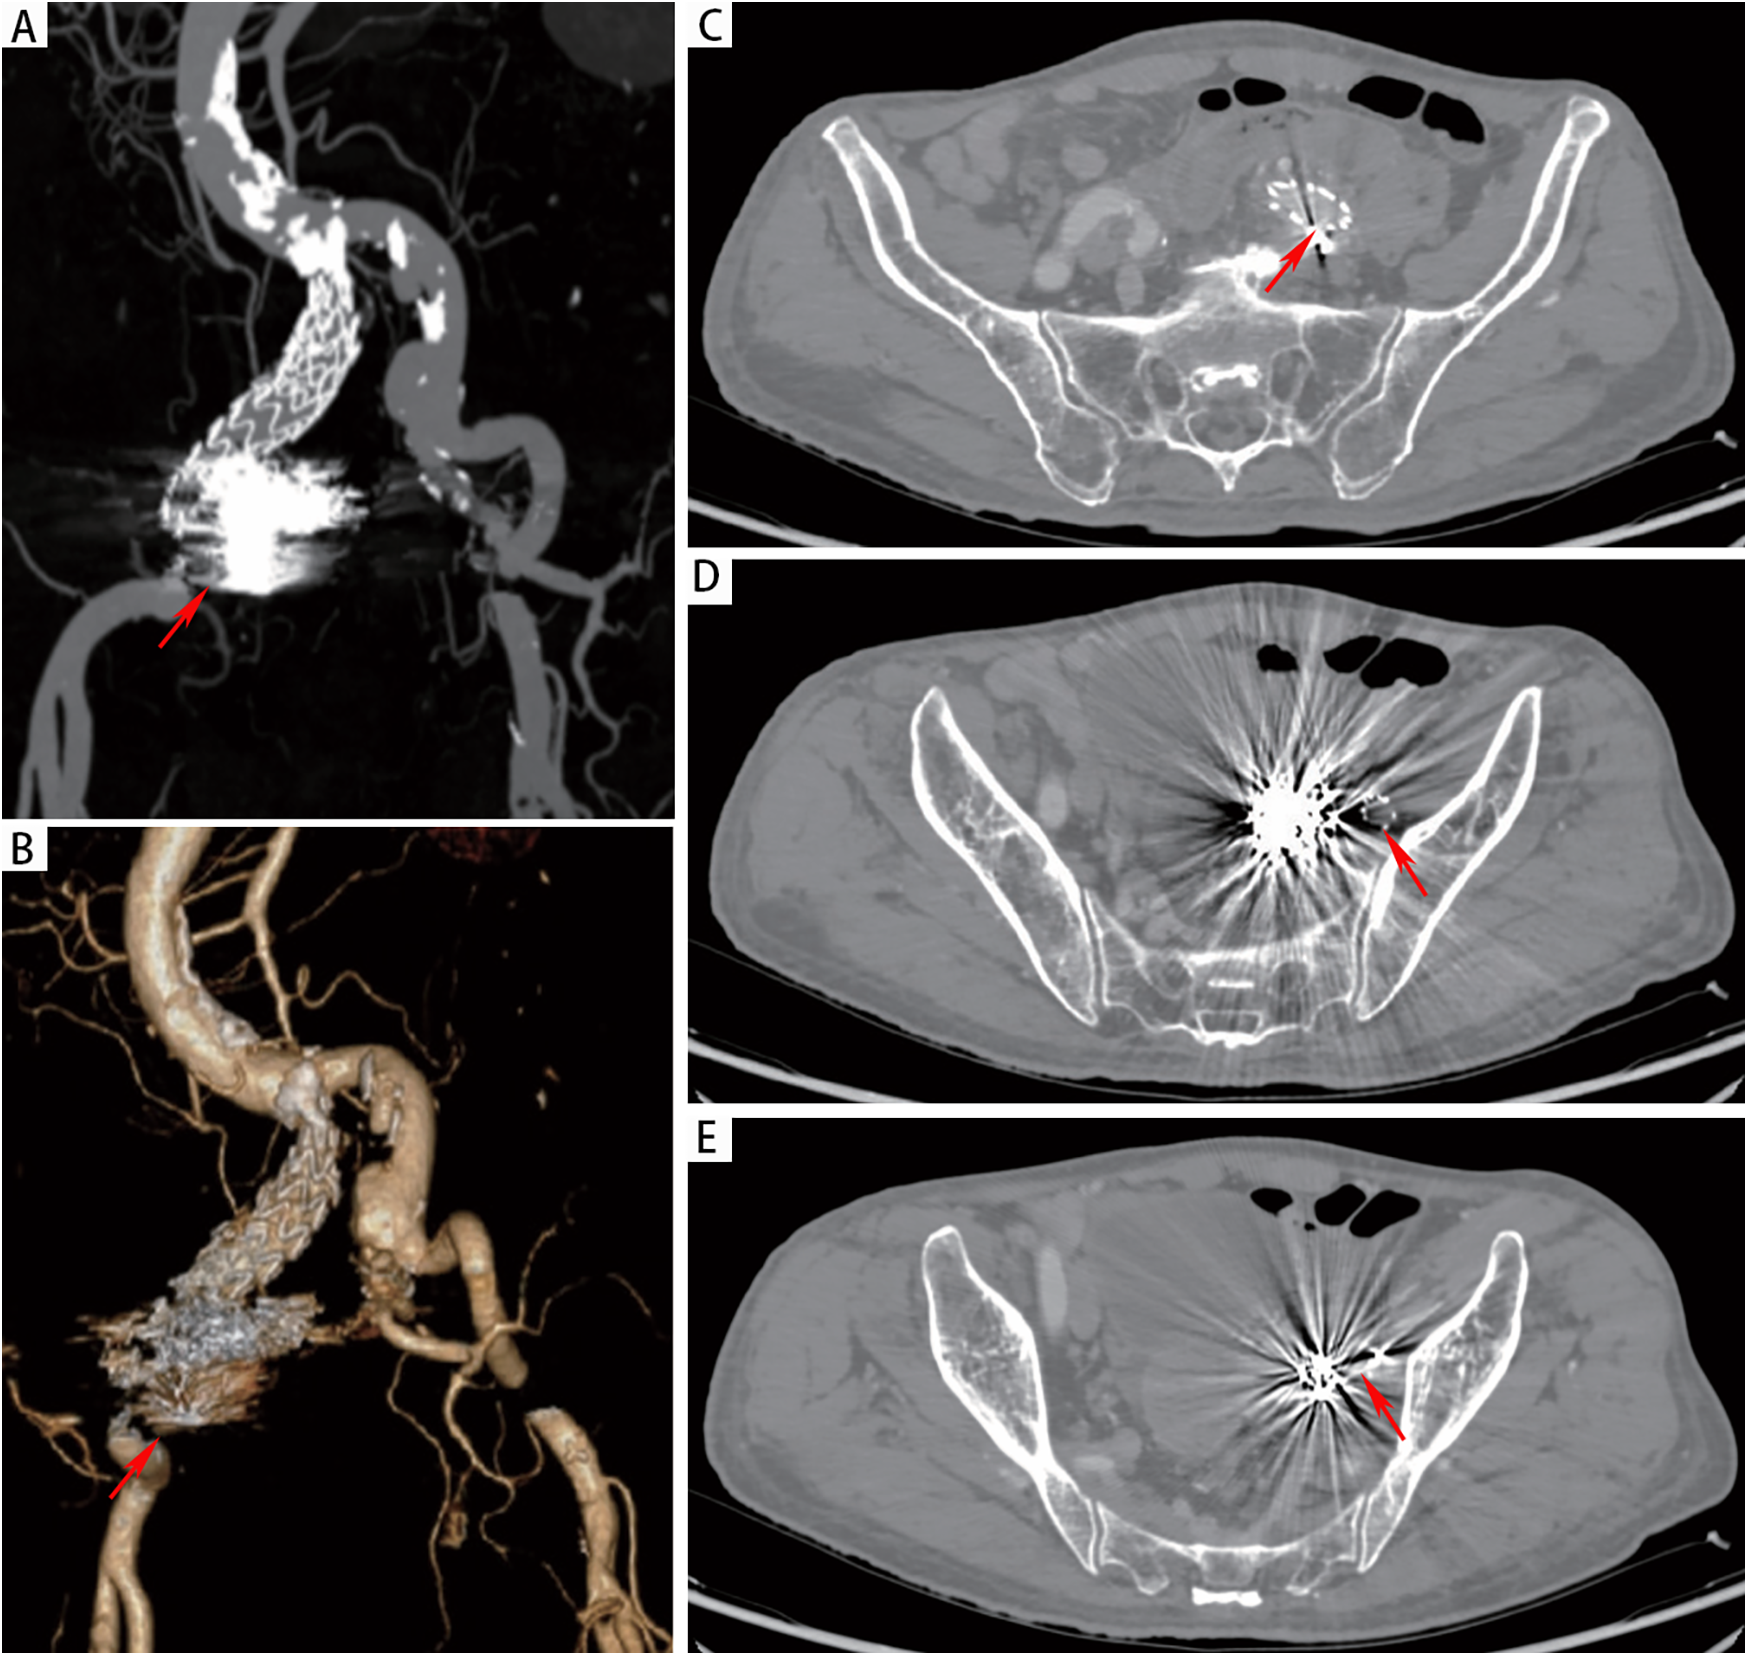

However, on the third day after the endovascular procedure, the patient experienced intermittent lower gastrointestinal bleeding (50–100 ml/day). Colonoscopy was subsequently performed, which revealed complete sloughing of the necrotic tissue at the enteric fistula site, exposing a fistula tract approximately 9 mm in diameter with active oozing (Figures 3A,B). Endoscopic clip hemostasis was then performed (Figure 3C). Following endoscopic hemostasis, the patient was maintained on parenteral nutrition and antibiotics, with close monitoring of hemoglobin levels and fecal occult blood tests. During this period, the patient remained afebrile without chills or fever. Three sets of blood cultures were negative. Hemoglobin levels gradually increased, and the frequency and volume of bloody stools steadily decreased. On post-endoscopic hemostasis day 9, the hemoglobin level was 90 g/L and the fecal occult blood test was negative. On day 11 after endoscopic hemostasis, follow-up endoscopy demonstrated complete closure of the fistula with only mild residual mucosal edema (Figure 3D). Biopsy specimens obtained during the initial emergency endoscopy showed chronic mucosal inflammation, focal necrosis with cholesterol deposition, mixed acute and chronic inflammatory cell infiltration, and multinucleated giant cell reaction. The patient resumed oral intake on day 12 after the initial surgery and was discharged on day 15 without complications. The discharge regimen included enteric-coated aspirin (100 mg/day) and levofloxacin (0.4 g/day). During a 7-month telephone follow-up, the patient reported normal bowel movements without fever or abdominal pain. A follow-up CT scan performed 7 months postoperatively demonstrated complete occlusion of the left internal iliac artery (Figure 4A), patency of the left external iliac artery (Figure 4B), and the stent without foci of gas (Figures 4C–E). The detailed sequence of therapeutic interventions is presented in the treatment timeline (Figure 5). Informed consent was obtained from both the patients and their families.

Figure 4

(A,B) CTA at 7 months postoperatively demonstrated patency of the left iliac artery stent and complete occlusion of the left internal iliac artery. (C-E) CT demonstrated absence of gas accumulation in the perigraft region.